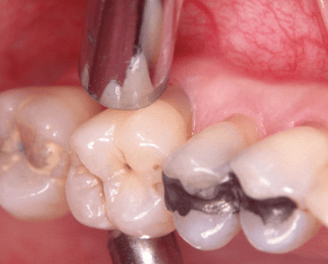

Eliminación de Factores locales de retención de Placa bacteriana

Consiste en identificar y eliminar elementos en la boca, como restos de alimentos o dientes rotos, tapaduras en mal estado que facilitan la acumulación de placa y contribuyen a enfermedades periodontales.